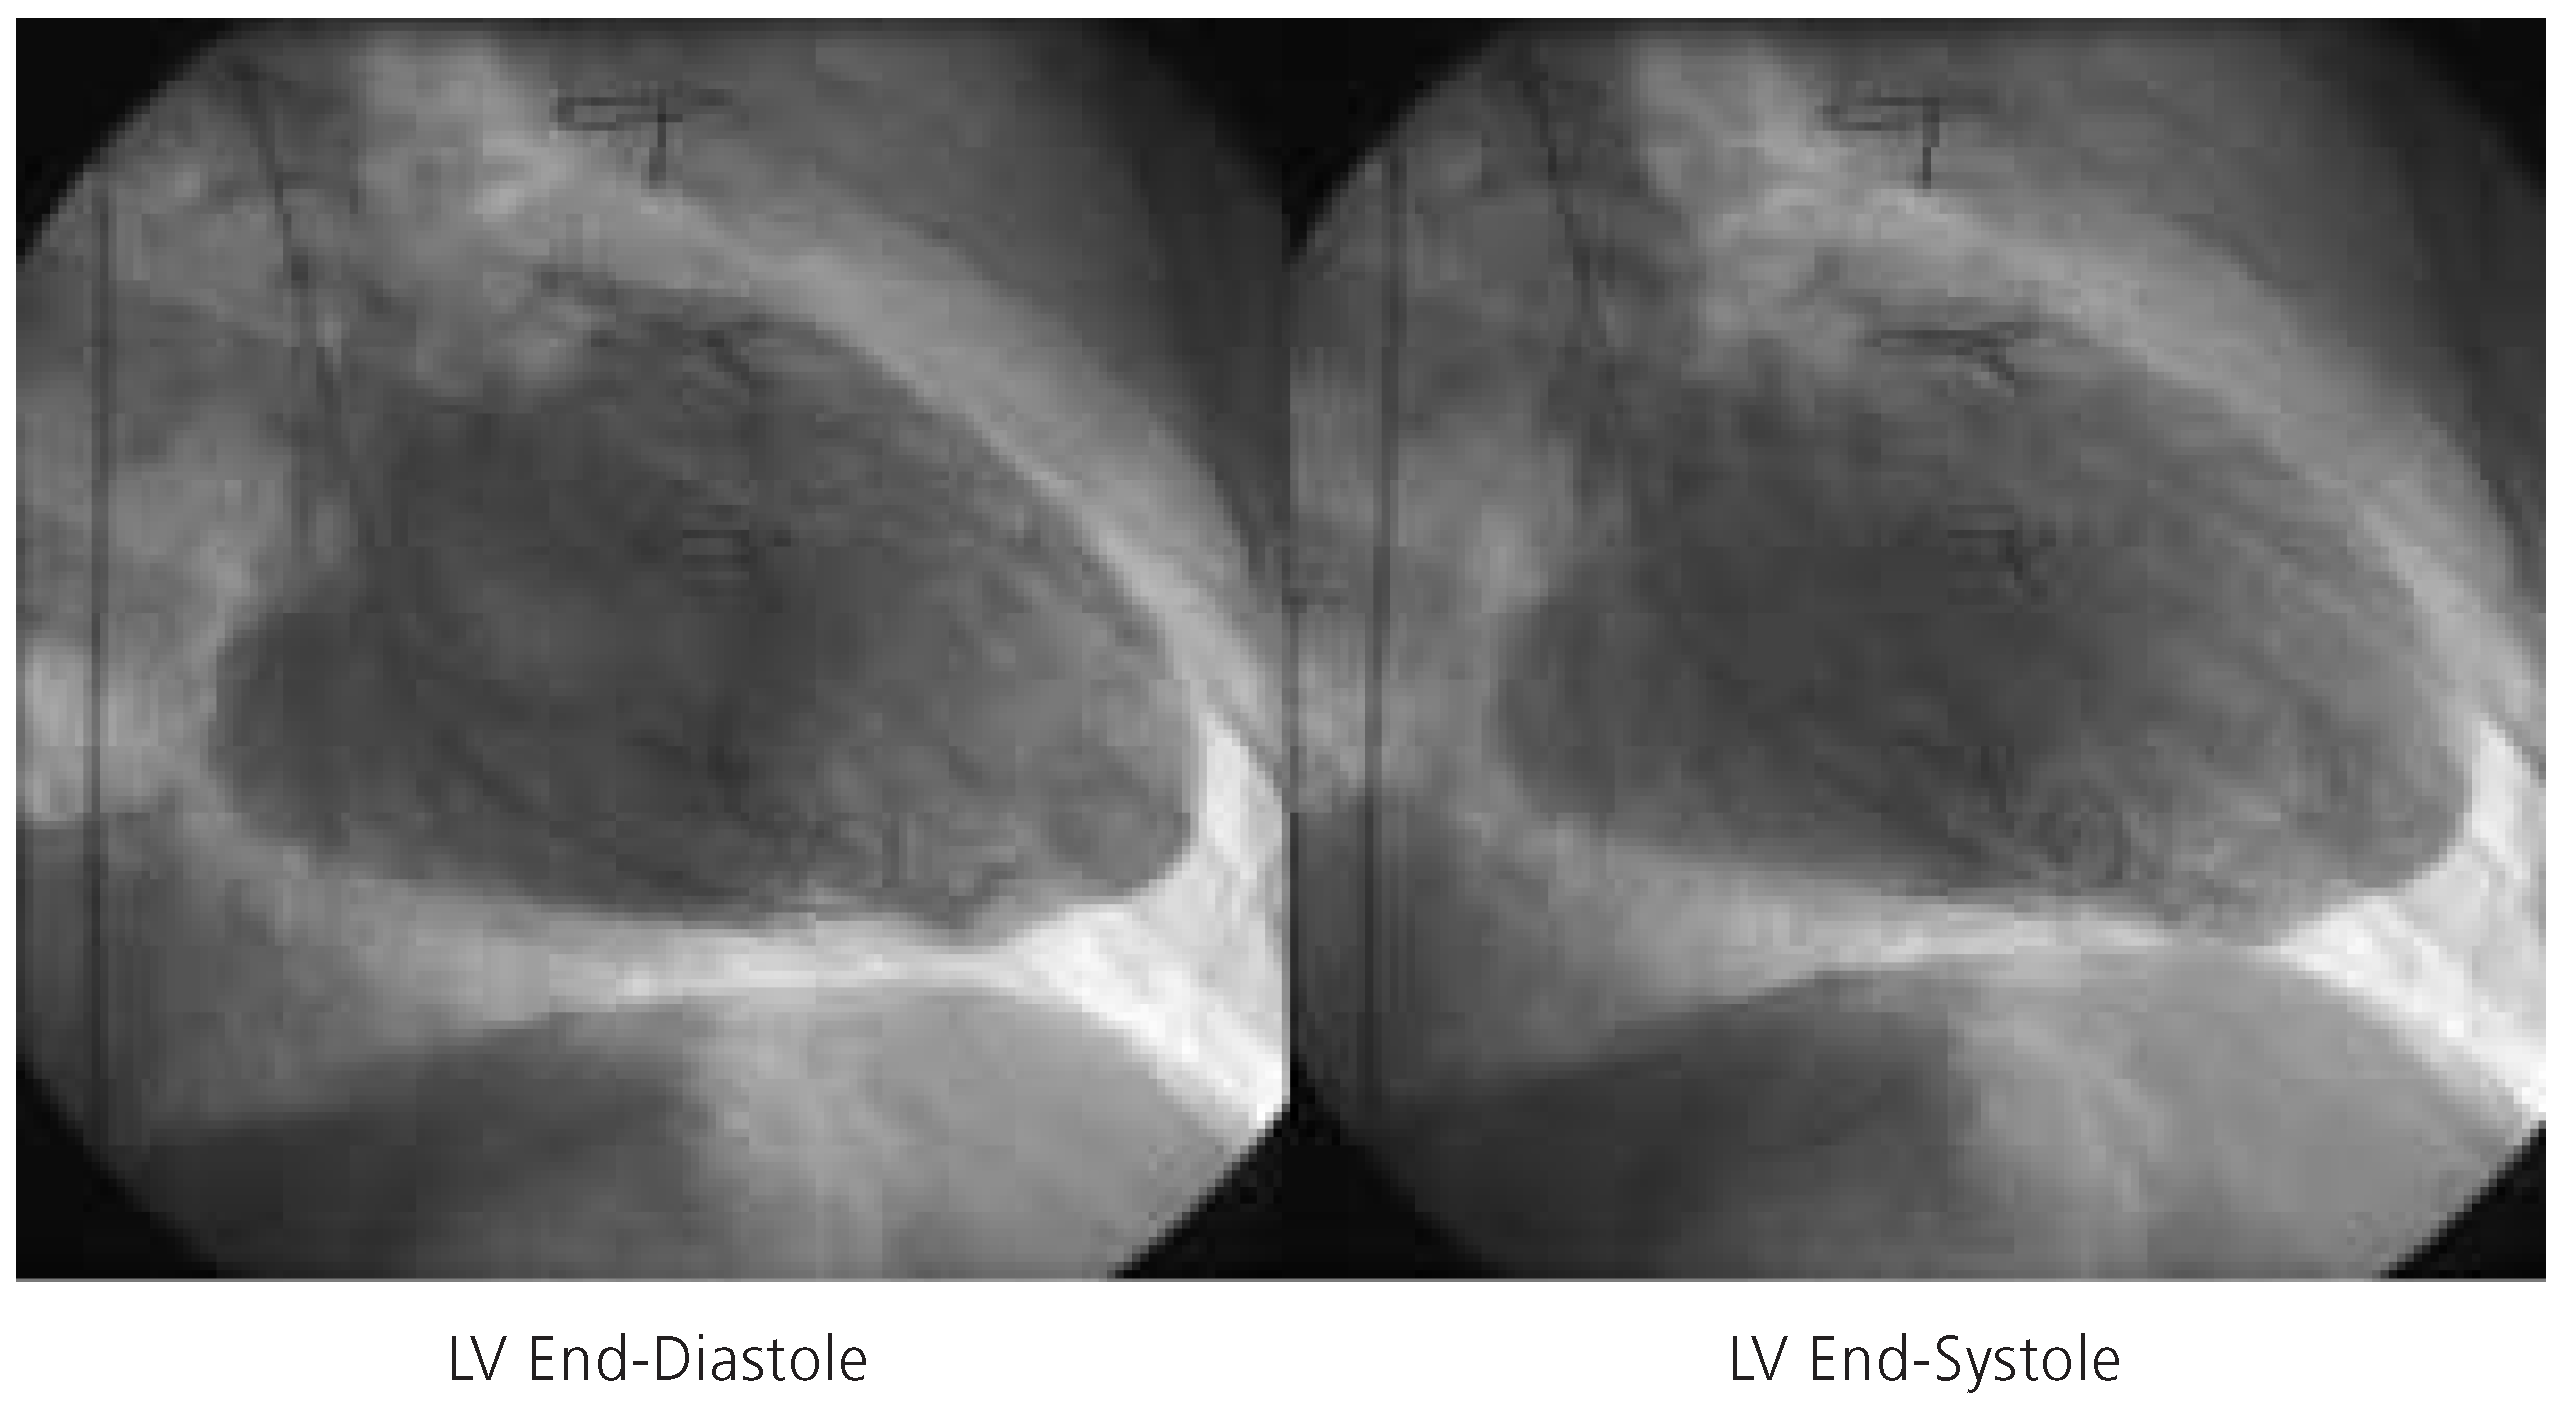

Figure 3.

Left ventricular end-diastolic frame (left) and left ventricular end-systolic frame (right) indicative of severely diminished left ventricular function (LVEF = 15%). LV = left ventricle.

A 64-year-old man with a long history of coronary artery disease was admitted due to crescendo angina pectoris and dyspnea on exertion. He had suffered an anterior and inferior myocardial infarction in 1986 and 1990, respectively, and undergone coronary artery bypass grafting with a left internal mammary artery to the left anterior descending coronary artery, and two saphenous vein grafts to the right coronary artery and the second marginal branch of the circumflex coronary artery in 1990. Cardiac catheterisation during this admission revealed native three vessel coronary artery disease with occlusion of the left anterior descending artery in the mid portion, three complex and high grade stenoses of the left circumflex artery, and proximal occlusion of the right coronary artery. The left internal mammary artery graft to the distal left anterior descending artery was patent, whereas the saphenous vein graft to the marginal branch of the left circumflex artery was occluded and the saphenous vein graft to the right coronary artery had been stented earlier for a high grade stenosis at the distal anastomosis. Left ventriculography revealed a severely diminished left ventricular function with an ejection fraction of 15% with dyskinesia of the entire anterolateral wall, akinesia of the inferior wall, and severe hypokinesia of the posterior and lateral wall (fig. 3). The left ventricular enddiastolic pressure measured 38 mm Hg.